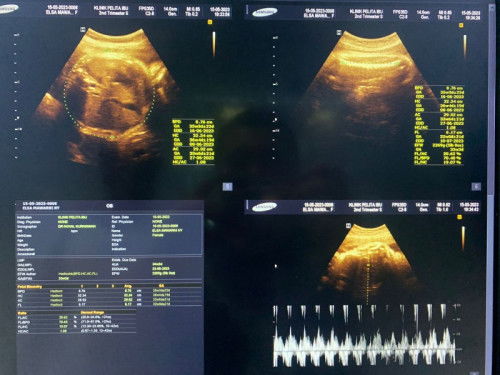

Umur khmilan dan bbj

Yg manah yabun umur khamilanku sm bbj kuu.

bbjnya 2269,klo umur kehamilanya GA bingung ya Bun bnyk gtu,aku aja ada 3 GA nya trs tanya dokter

bbj nya 2269g kalau umur kehamilan nya dari GA itu 33w 3d bun

usia ny 33wek2day